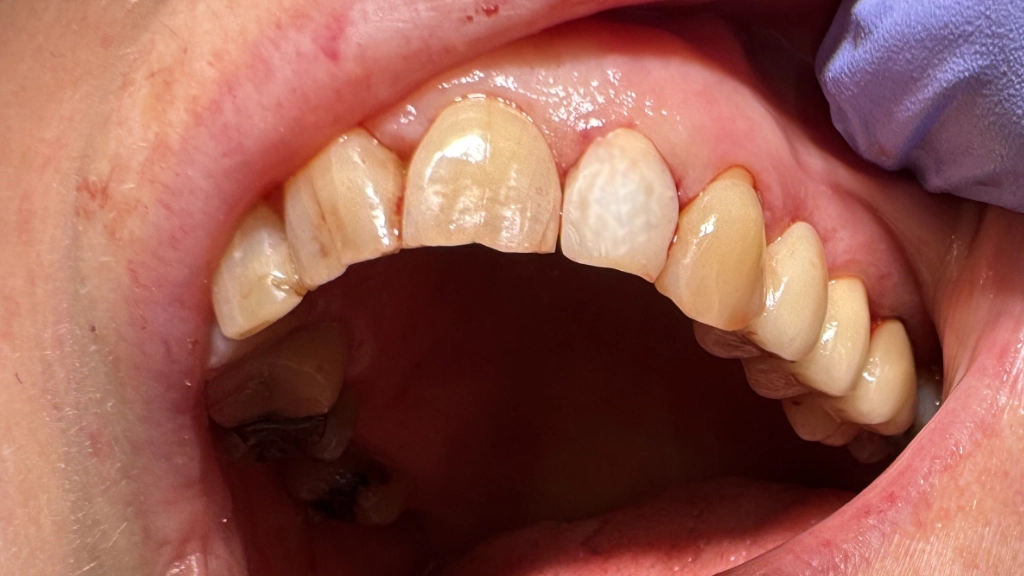

De noodkroon

De tandarts plaatst een tijdelijk abutment:

We hebben reeds een kapje voorbereid voor de vorm, het kapje wordt vastgezet aan de witte stift en afgewerkt/gepolijst:

Van dichtbij oogt zo'n noodkroon niet erg fraai, onthoud dat het een stukje plastic is. Op gespreksafstand oogt de tand wel normaal en eerlijk gezegd toch wat netter dan zo'n missende tand!

De röntgenfoto laat een mooie positie zien. (Op de foto lijkt deze niet precies in het midden te staan, maar dit is absoluut vertekening door de inzetrichting van de röntgenbuis). Aan weerszijden van het implantaat is de tandkas van de oude wortel goed zichtbaar. De tijdelijke stift is niet zichtbaar op röntgenfoto's.